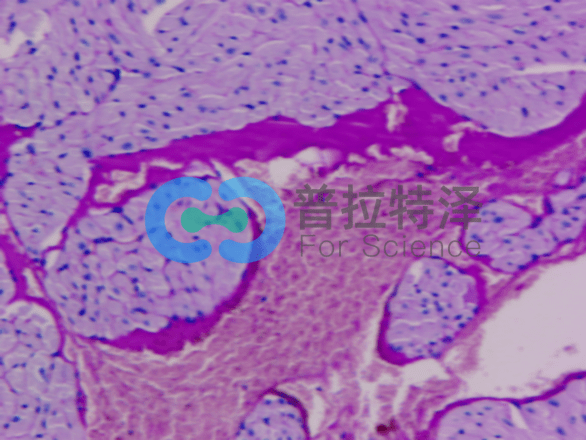

首先,我們來了解PAS染色的基本原理。它利用過碘酸將細(xì)胞中的多糖類物質(zhì)氧化,再通過雪夫試劑與氧化后的多糖結(jié)合,形成特征性的紅色或紫色沉淀。這種沉淀能夠清晰地顯示出細(xì)胞中的多糖類物質(zhì)分布和含量,從而幫助我們了解細(xì)胞的代謝狀態(tài)和功能特點(diǎn)。

在PAS染色實(shí)驗(yàn)的第一個(gè)層次,我們需要關(guān)注實(shí)驗(yàn)步驟和操作要點(diǎn)。實(shí)驗(yàn)過程中,首先需要對(duì)樣本進(jìn)行固定和脫水處理,以確保細(xì)胞的形態(tài)和結(jié)構(gòu)不受破壞。然后,利用過碘酸對(duì)細(xì)胞進(jìn)行氧化處理,使多糖類物質(zhì)發(fā)生特定的化學(xué)變化。接著,通過雪夫試劑與氧化后的多糖結(jié)合,形成可見的沉淀。最后,通過顯微鏡觀察樣本的染色情況,分析細(xì)胞中的多糖類物質(zhì)分布和含量。

在第二個(gè)層次,我們將探討PAS染色實(shí)驗(yàn)在細(xì)胞結(jié)構(gòu)與功能研究中的應(yīng)用。多糖類物質(zhì)在細(xì)胞中扮演著重要的角色,它們不僅是細(xì)胞壁和細(xì)胞膜的主要成分,還參與細(xì)胞的能量代謝和信號(hào)傳導(dǎo)等過程。因此,通過PAS染色實(shí)驗(yàn),我們可以觀察到細(xì)胞中多糖類物質(zhì)的分布情況,進(jìn)而推斷出細(xì)胞的生理狀態(tài)和功能特點(diǎn)。這對(duì)于研究細(xì)胞的生長、分化和凋亡等過程具有重要意義,也為疾病的診斷和治療提供了重要的依據(jù)。